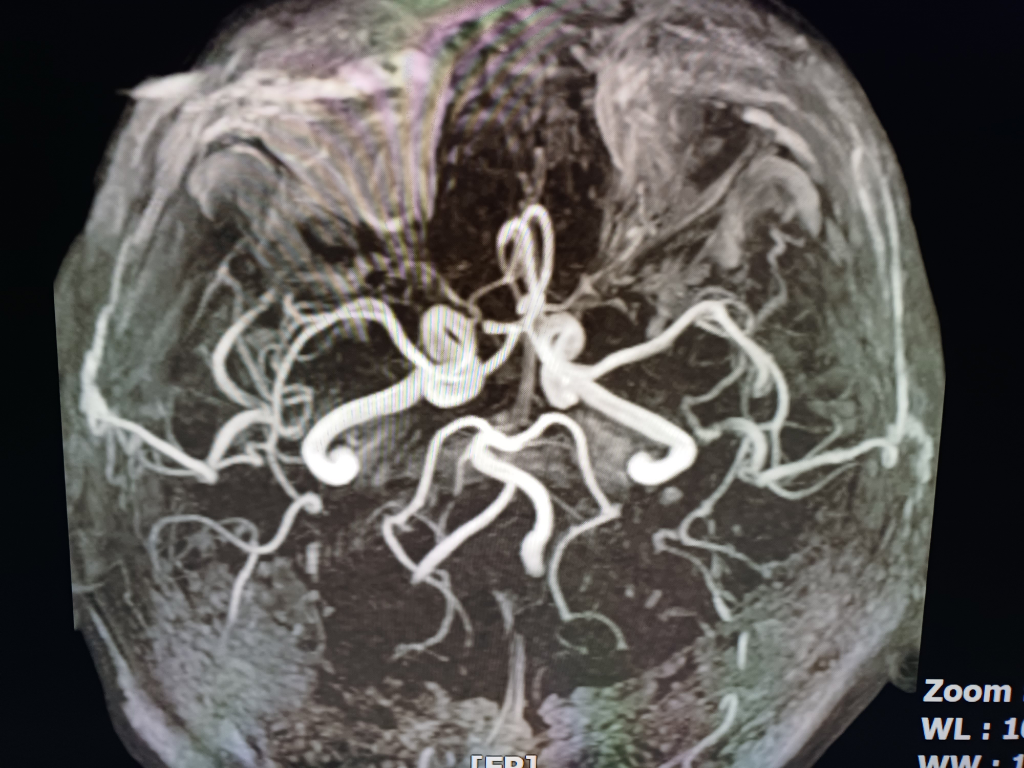

뇌 mri mra를 찍었는데 전문가분들의 고견을 구합니다.

안녕하세요.불편한 어지러움이 한달이상 지속되어 혹뇌쪽 이상이 아닌가 싶어 오늘급하게 mri mra를 촬영하고 왔습니다.결과를 바로 확인할수 있는줄 알았으나 일주일정도 기다려야 판독이 나온다하여 급한 마음에 사진 몇장 첨부하오니 답변해주시면 감사하겠습니다!!

• 1번 째 사진

업로드해주신 MRI 및 MRA 영상은 특별히 이상한 소견이 보이지 않습니다

뇌실질에 이상소견 없으며 뇌혈관이 막여있거나 좁아진 부분도 보이지 않습니다

현재 올려주신 사진만으로는 아주 큰 병변 이 있어 보이지는 않으나, MRI의 경우 연속된 단면을 모두 봐야 병변을 정확히 확인할 수 있으므로 해당 사진들만으로는 병변의 유무를 모두 다 확인 불가능합니다. 추후 판독을 기다려 보시기 바랍니다.